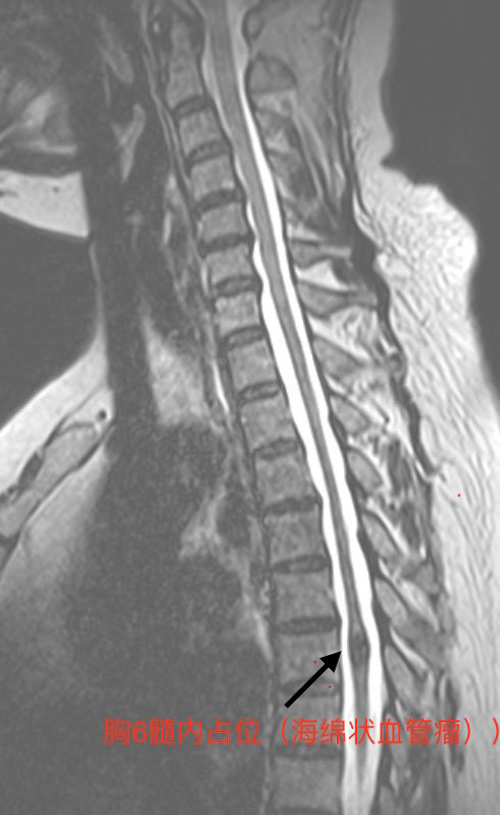

近日,兰州石化总医院(甘肃中医药大学第四附属医院)神经外科团队在李立强主任的带领下,成功为一名复杂脊髓血管畸形患者实施高难度切除术。该病例因畸形结构罕见、手术风险极高,曾被业内视为“生命禁区”。凭借精湛的技术与多学科协作,团队突破难关,术后患者恢复良好,标志着医院在脊髓神经外科领域再攀高峰。

脊髓血管畸形是一种发病率不足千分之一的罕见疾病,因血管结构异常可导致脊髓受压、出血甚至永久性瘫痪。本例患者畸形血管团位置深、毗邻重要神经传导束,且异常血管错综复杂,稍有不慎即可能引发术中大出血或神经功能损伤。此类病例的诊治对医疗团队的技术水平与应急能力提出极致挑战。

术前:放射影像科通过MRI平扫及增强锁定畸形范围,神经外科、骨伤科、麻醉手术科、心内科及重症医学科多学科讨论,明确手术及围手术期风险,制定应急处理方案;